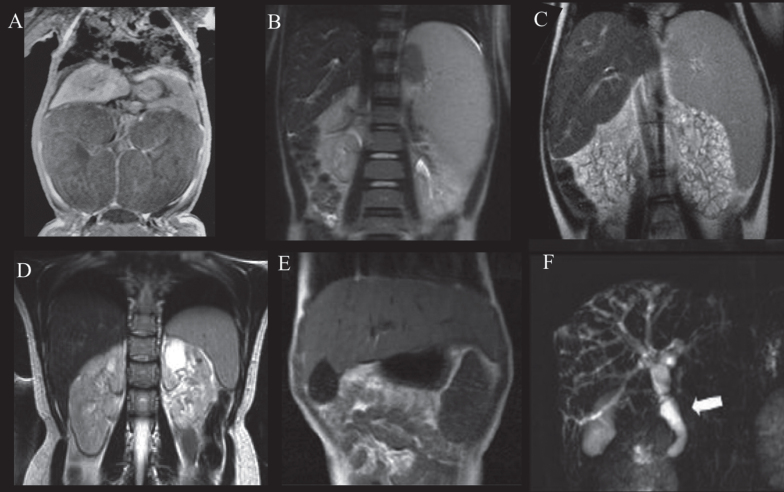

Abstract Image